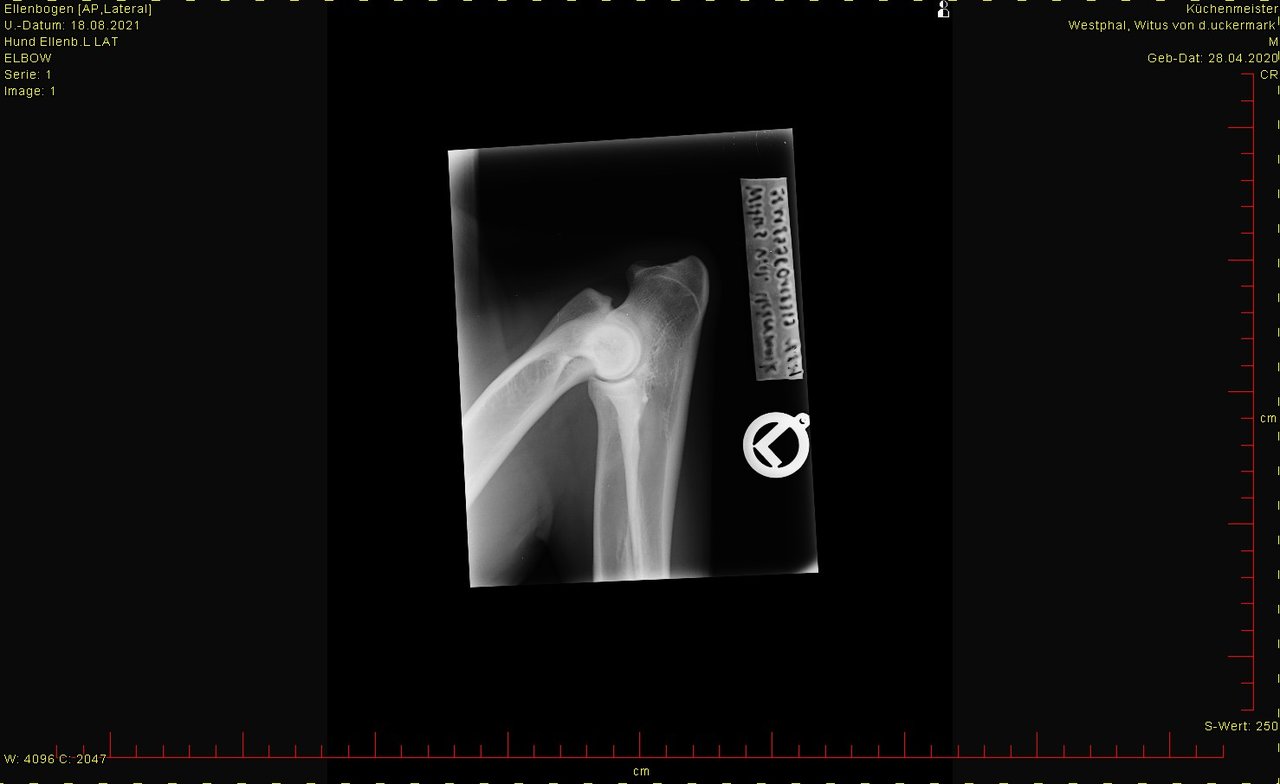

hier das Bild von der Hüfte. Ist HD-Aufnahme, kann man groß ansehen.

Was sagt Ihr dazu?

Aber weil Ihr ja die Bilder mal sehen wolltet hätte es ja sein können, das da jemand einen Blick für hat.

Bei den Ellenbogen traue ich mir keine Bewertung zu, finde aber, dass Hüfte und Rücken okay sind